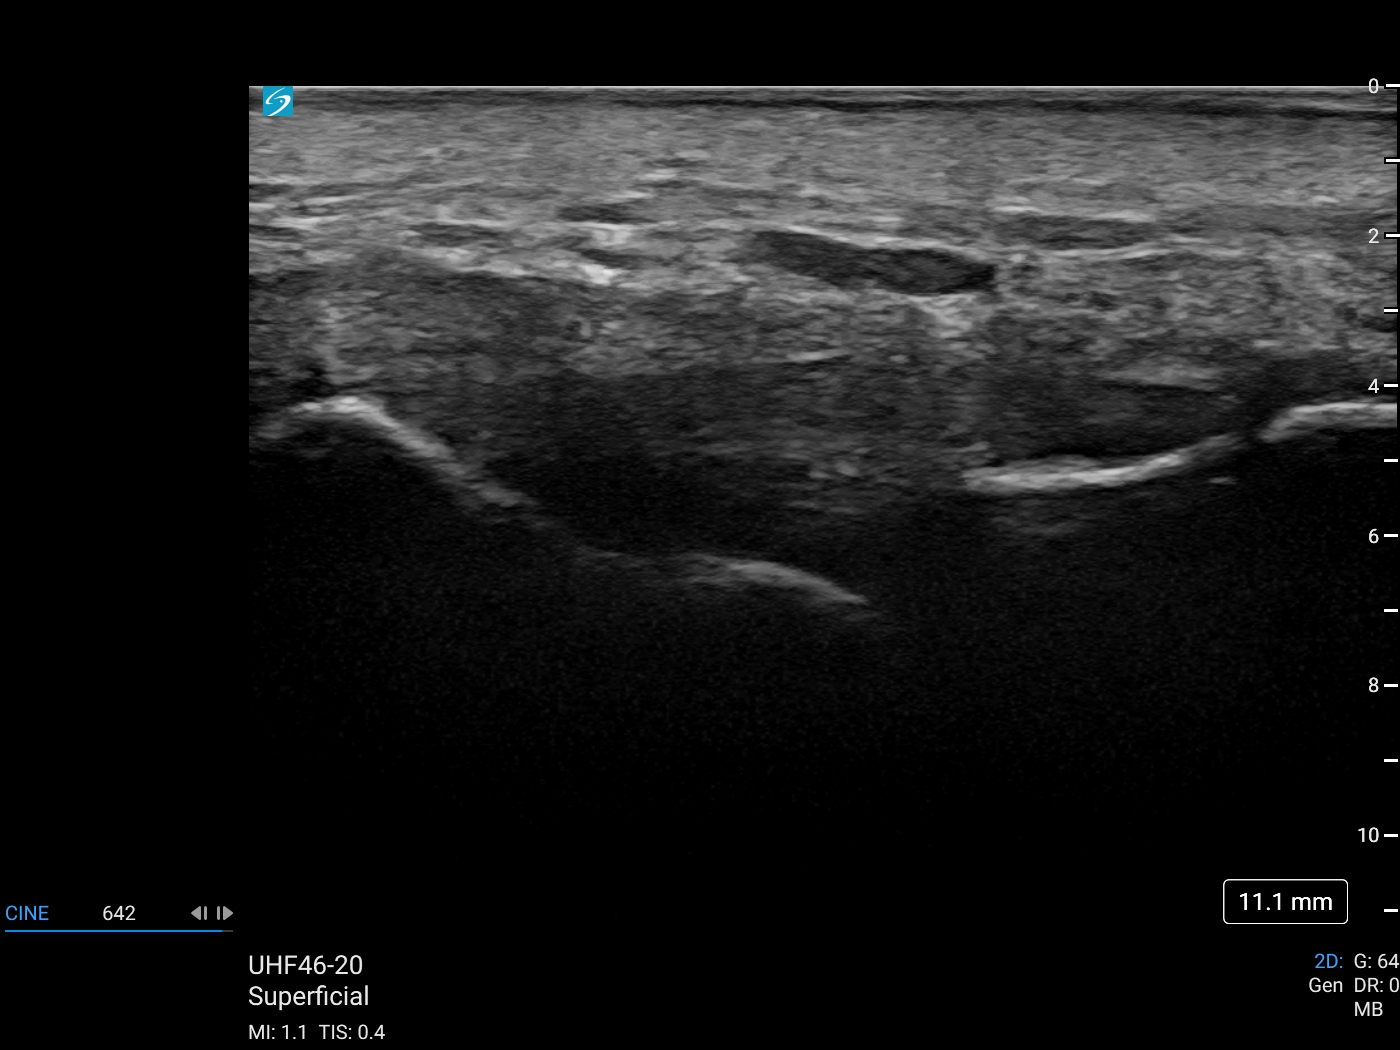

Ulnar Collateral Ligament with UHF 46-20MHz